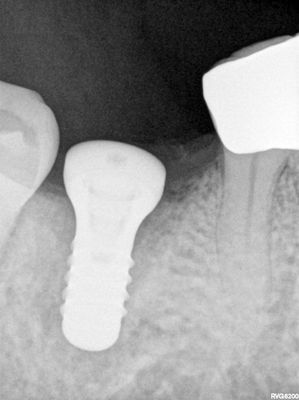

root tip removed, all granulation removed, osteotomy underprepared due to existing defect from root tip, implant placed with good stabiltiy, tissue level used to bring up connection as lingual bone is 1-2mm lower than buccal. Defect obliterated by implant .